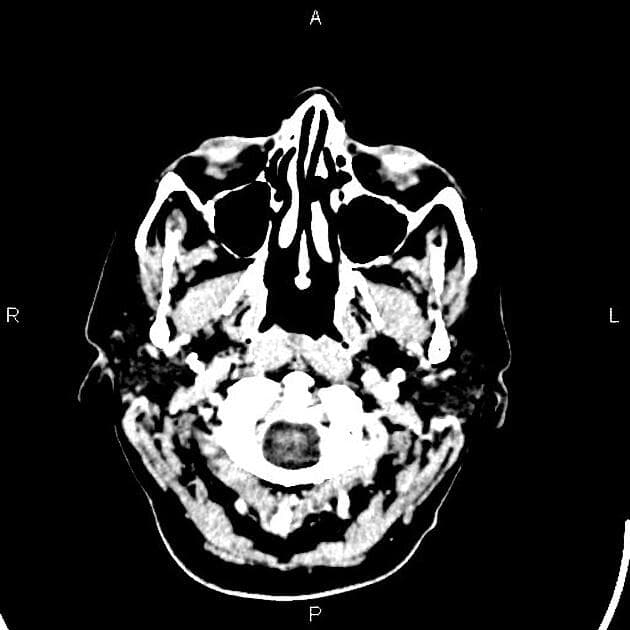

Hình ảnh CT này cho thấy hai tổn thương dạng tròn có bắt thuốc dạng viền ở vùng thái dương phải. Ngoài ra còn có phù quanh tổn thương. BÀN LUẬN: Trường hợp này cho thấy một tổn thương di căn não từ ung thư vú.

Di căn não xảy ra ở một tỷ lệ đáng kể bệnh nhân ung thư vú giai đoạn tiến triển. Về mặt chẩn đoán hình ảnh, chúng thường xuất hiện dưới dạng nhiều khối choán chỗ giới hạn rõ với phù vận mạch rộng xung quanh. Kiểu tăng quang có thể là dạng đặc hoặc bắt thuốc dạng viền.